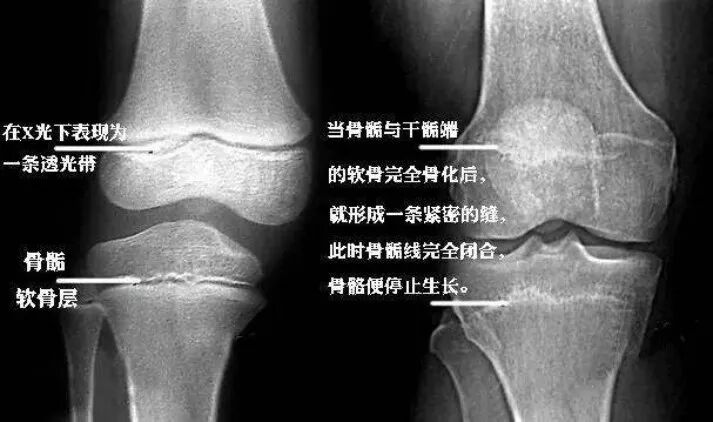

但并不是所有人注射了生长激素都能达到这么理想的效果,有些孩子,用完药只长了3cm↓男孩小五,15岁,爸爸身高180cm,妈妈身高165cm,然而15岁的小五只有160cm。骨龄片显示,小五现在的骨骺线已经呈现半闭合状态,即便使用生长激素治疗身高增长最多也不会超过5cm。父母想做最后的努力:“试试吧医生,能长高多少是多少,总比一点不张要好吧!”就这样,小五用药半年后,身高只长高了3cm,上个月拍骨龄片显示骨垢线已经完全闭合,终身高定格在163cm。效果因人而异还不是关键,家长们最最担心的是,个子高了,却要用其他不良反应来换↓面对正反两种完全不同的声音,家长该如何科学认识生长激素、做出适合自家娃的判断呢?下面这部分王春林主任的独家专访,或许会帮到你。

孩子身高70%来自父母遗传影响8、“青春期晚期”有什么表征吗?家长如何判断孩子是否进入青春期晚期?主要特征是生长速率放慢。比如之前1个月长1厘米,现在3个月才长不到2厘米,那就说明孩子生长期快结束了,这个时候就一定抓牢最后的治疗时机。千万不能等到一点都不长了,骨龄片发现骨骺线已经闭合,那就没办法了。所以青春期的身高管理很要紧,家长一定要及时关注。